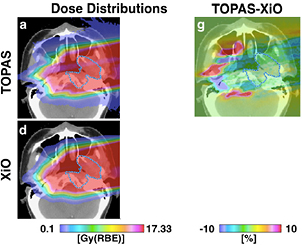

Because proton therapy plans are not optimized in RBE-weighted dose, expressed in Gy(RBE)7, biology is considered independently from the physics driven planning process using the RBE = 1.1 approximation and considering uncertainties. In C-ion therapy, instead, plans are optimized using the Gy(RBE). Essentially two different models are used for the calculation of the Gy(RBE): the Japanese centers use a model developed at NIRS, where the shape of the SOBP is based on in vitro cell killing experiments. The curve is then normalized using a region in the SOBP which is isoeffective to neutrons, whose clinical RBE was determined as 3 from previous clinical experience in Japan (Matsufuji et al 2007). On the other hand, the GSI Helmholtz Center in Darmstadt (Germany) developed a specific biophysical model (local effect model, or LEM), which predicts the RBE for different ions and tumor types starting from the corresponding clinical photon data and an amorphous track structure model (Krämer and Scholz 2000). Amorphous track structure models use average dose distributions along the track of the heavy ions, assuming that the dose decreases as r−2, where r is the track radius. Once the physical dose distribution is described, the biological response can be derived from x-ray survival curve, and the model can predict the effect of any ion. Already introduced by Bob Katz in the 60s (Butts and Katz 1967), these models are sometimes criticized by supporters of micro- or nano-dosimetry because they do not account for the high heterogeneity of the dose distribution at the nm level, already visible with x-rays (Beuve 2009). However, recent measurements of DNA damage distribution in vivo show that the predicted radial dose distribution corresponds to an observed biological damage distribution (Mirsch et al 2015). Amorphous track structure approximations remain therefore a simple and valid tool for prediction of charged particle effects starting from x-ray radiosensitivity. The LEM is able to reproduce the RBE of light and heavy ions for inactivation of cells with different intrinsic radiosensitivity, and has been improved many times in the past years (Grün et al 2012). It is currently being used in the C-ion therapy centers in Germany (Heidelberg and Marburg), Italy (Pavia), and China (Shanghai). An experimental intercomparison between NIRS and GSI using in vitro cells and mice provided comparable results, in agreement with the measured RBE (Uzawa et al 2009). However, the two models give different predictions of the Gy(RBE) when different fractionation schemes and tissue radiosensitivity are compared (Fossati et al 2012; Steinsträter et al 2012). In order to make use of the full potential of carbon beam scanning, NIRS has recently introduced a modified microdosimetric kinetic model (MKM) that can adapt optimization procedures to various biological parameters (Inaniwa et al 2015). This is particularly important for hypofractionation regimens, where the use of a dose-dependent RBE is necessary to take into account the reduced RBE at high dose/fraction (Friedrich et al 2014).

2.5.3. Treatment planning: physics and biology.

Treatment of a patient with pencil beam scanning is uniquely tailored for that patient and requires many different parameters. Each of these parameters has uncertainties. The error on the particle stopping power in a given tissue can shift 3–5% the prescribed range. Monte Carlo codes can be the ideal tools for precise plan calculations, but they must be faster to find daily clinical applications, and need accurate reaction cross-sections in useful target materials for the energy range of interest. Measurements of double-differential fragmentation cross sections are essential for heavy ion therapy, while target fragmentation is important also in protontherapy. These are 'classical' nuclear physics measurements, even if they are time-consuming and complex, and may represent a major contribution of 'old' nuclear physics to 'new' cancer therapy. In addition, new centers will try to exploit different ions beyond 1H and 12C, and treatment plans should add the ion atomic number Z to the optimization. However, the physical dose in Gy for charged particles does not reflect the biological effects in the tumor and the normal tissue. The plan optimization must also include the biological effectiveness of the beam, taking into account the intra-tumoral heterogeneity (hypoxia, cancer stem cell niches, etc). Development of robust radiobiological models is essential to exploit the full benefit of particle therapy, and require a careful physical characterization of the beam interaction down to the nm size. Beyond the RBE, major breakthrough can be expected by particle radiobiology, e.g. in the emerging field of radioimmunotherapy, and new biophysical models will be necessary to incorporate these new data.